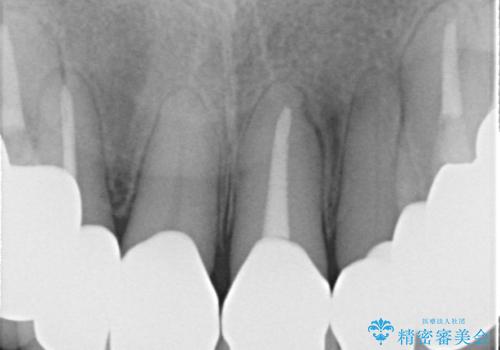

時間をかけ、妥協なく治療を行い、今後の再治療の可能性を極力少なくするために、

費用や時間といった労力がかかってしまうのは当然のことです。

- 根管治療により類似の全ての症例の問題が解決するわけではなく、症例はあくまでも一例です

- 根管治療により痛みや腫れがひかない事や、術後に痛みや腫れが生じる事、治療によるファイル破折やパーフォレーションなどの偶発症、術後の歯根破折を生じる可能性もあります